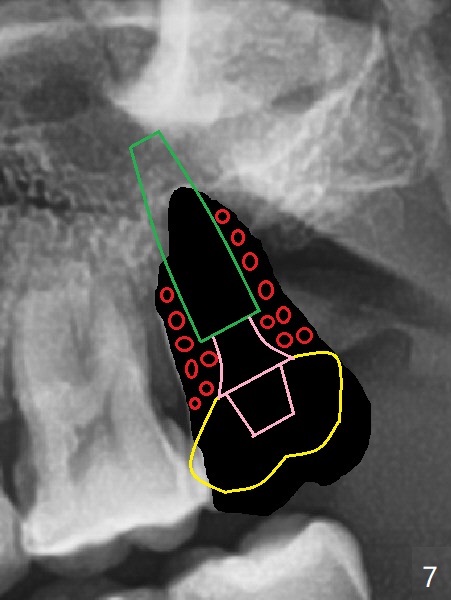

步骤四:制作临时修复物固定骨粉(图七:黄色)。